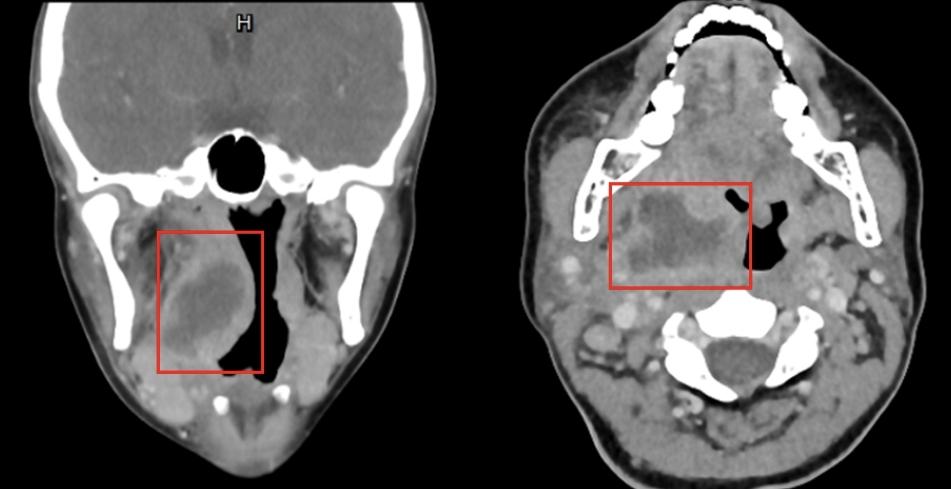

很快,颈部增强CT结果也证实:在小张右侧颈部,确实有一个大大的“鸡蛋”,里面的液体是由于细菌感染导致的脓液,它牢牢占据了扁桃体上窝的空间,诱发周围正常结构的强烈炎症反应,这才导致剧烈咽痛。